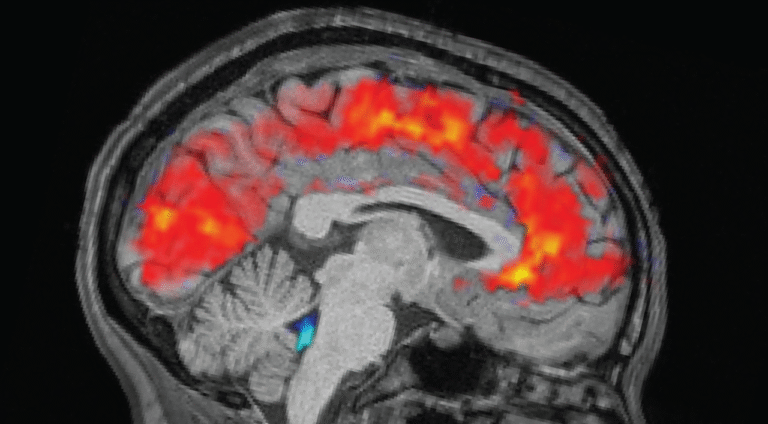

The rested individuals slept for 6.5 to 9 hours at home, while sleep-deprived individuals were kept awake all night in the laboratory. In the morning before each trial, the team strapped electroencephalogram (EEG) caps onto the participants to record their brain waves with electrodes. Simultaneously, the participants underwent functional MRI (fMRI) scans to reveal patterns in blood and CSF flow in the brain. Eye-trackers measured the participants’ pupil size.

As expected, participants took longer to notice the stimuli when tired, and missed the cues more often than they did when they were well rested. But the team was surprised to see giant pulses of CSF in the exhausted individuals, alongside patterns of slow brain waves — both of which are normally observed in non-REM sleep.

Specifically, the patterns resembled that seen as a person shifts from stage N1 into N2, the first two of three stages of non-REM sleep that people experience each slumber. “This was something that previously we’d only seen on this scale during sleep,” Lewis said.

The CSF flow was closely linked to pupil size, with the large inward flow following pupil dilation and the outflow coming after pupil constriction. This connection was more pronounced in sleep-deprived individuals, which could suggest the body’s circulatory system underpins this coupling, the authors wrote. The CSF flows also coincided with when individuals zoned out during tasks.